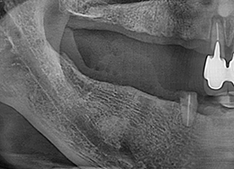

서울탑플란트 치료사례

어떠한 임플란트 케이스도 문제없이 치료가 가능합니다

서울탑플란트치과에서는 정기적인 점검을 통해

임플란트 주위 잇몸과 치조골을 건강하게 유지할 수 있도록 관리하고 있습니다.